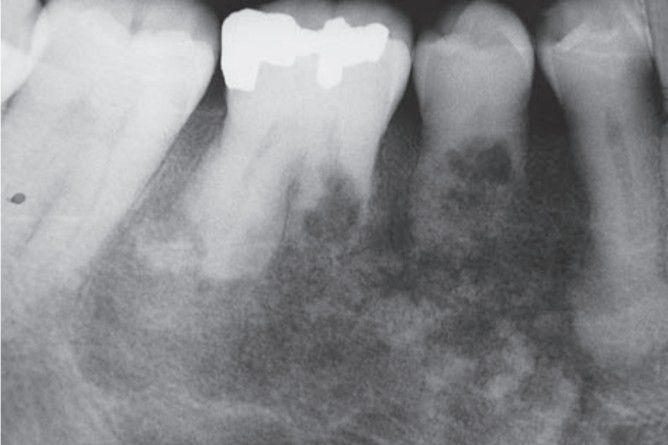

Pagets disease

Pagets disease of mandible associated with root resorption.